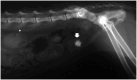

Practical relevance: Uroliths occur commonly in the bladder and/or urethra of cats and can be lifethreatening if urethral obstruction occurs. Calcium oxalate accounts for 40-50% of urocystoliths and these stones are not amenable to medical dissolution; therefore, removal by surgery or minimally invasive techniques is required if uroliths must be treated. Medical protocols for prevention involve decreasing urine saturation for minerals that form uroliths.

Basic concepts: In order to develop rational and effective approaches to treatment, abnormalities that promote urolith formation must be identified, with the goal of eliminating or modifying them. It is important, therefore, to understand several basic concepts associated with urolithiasis and the factors that promote urolith formation that may be modified with medical treatment; for example, the state of urinary saturation, modifiers of crystal formation, potential for multiple crystal types, and presence of bacterial infection or urinary obstruction.